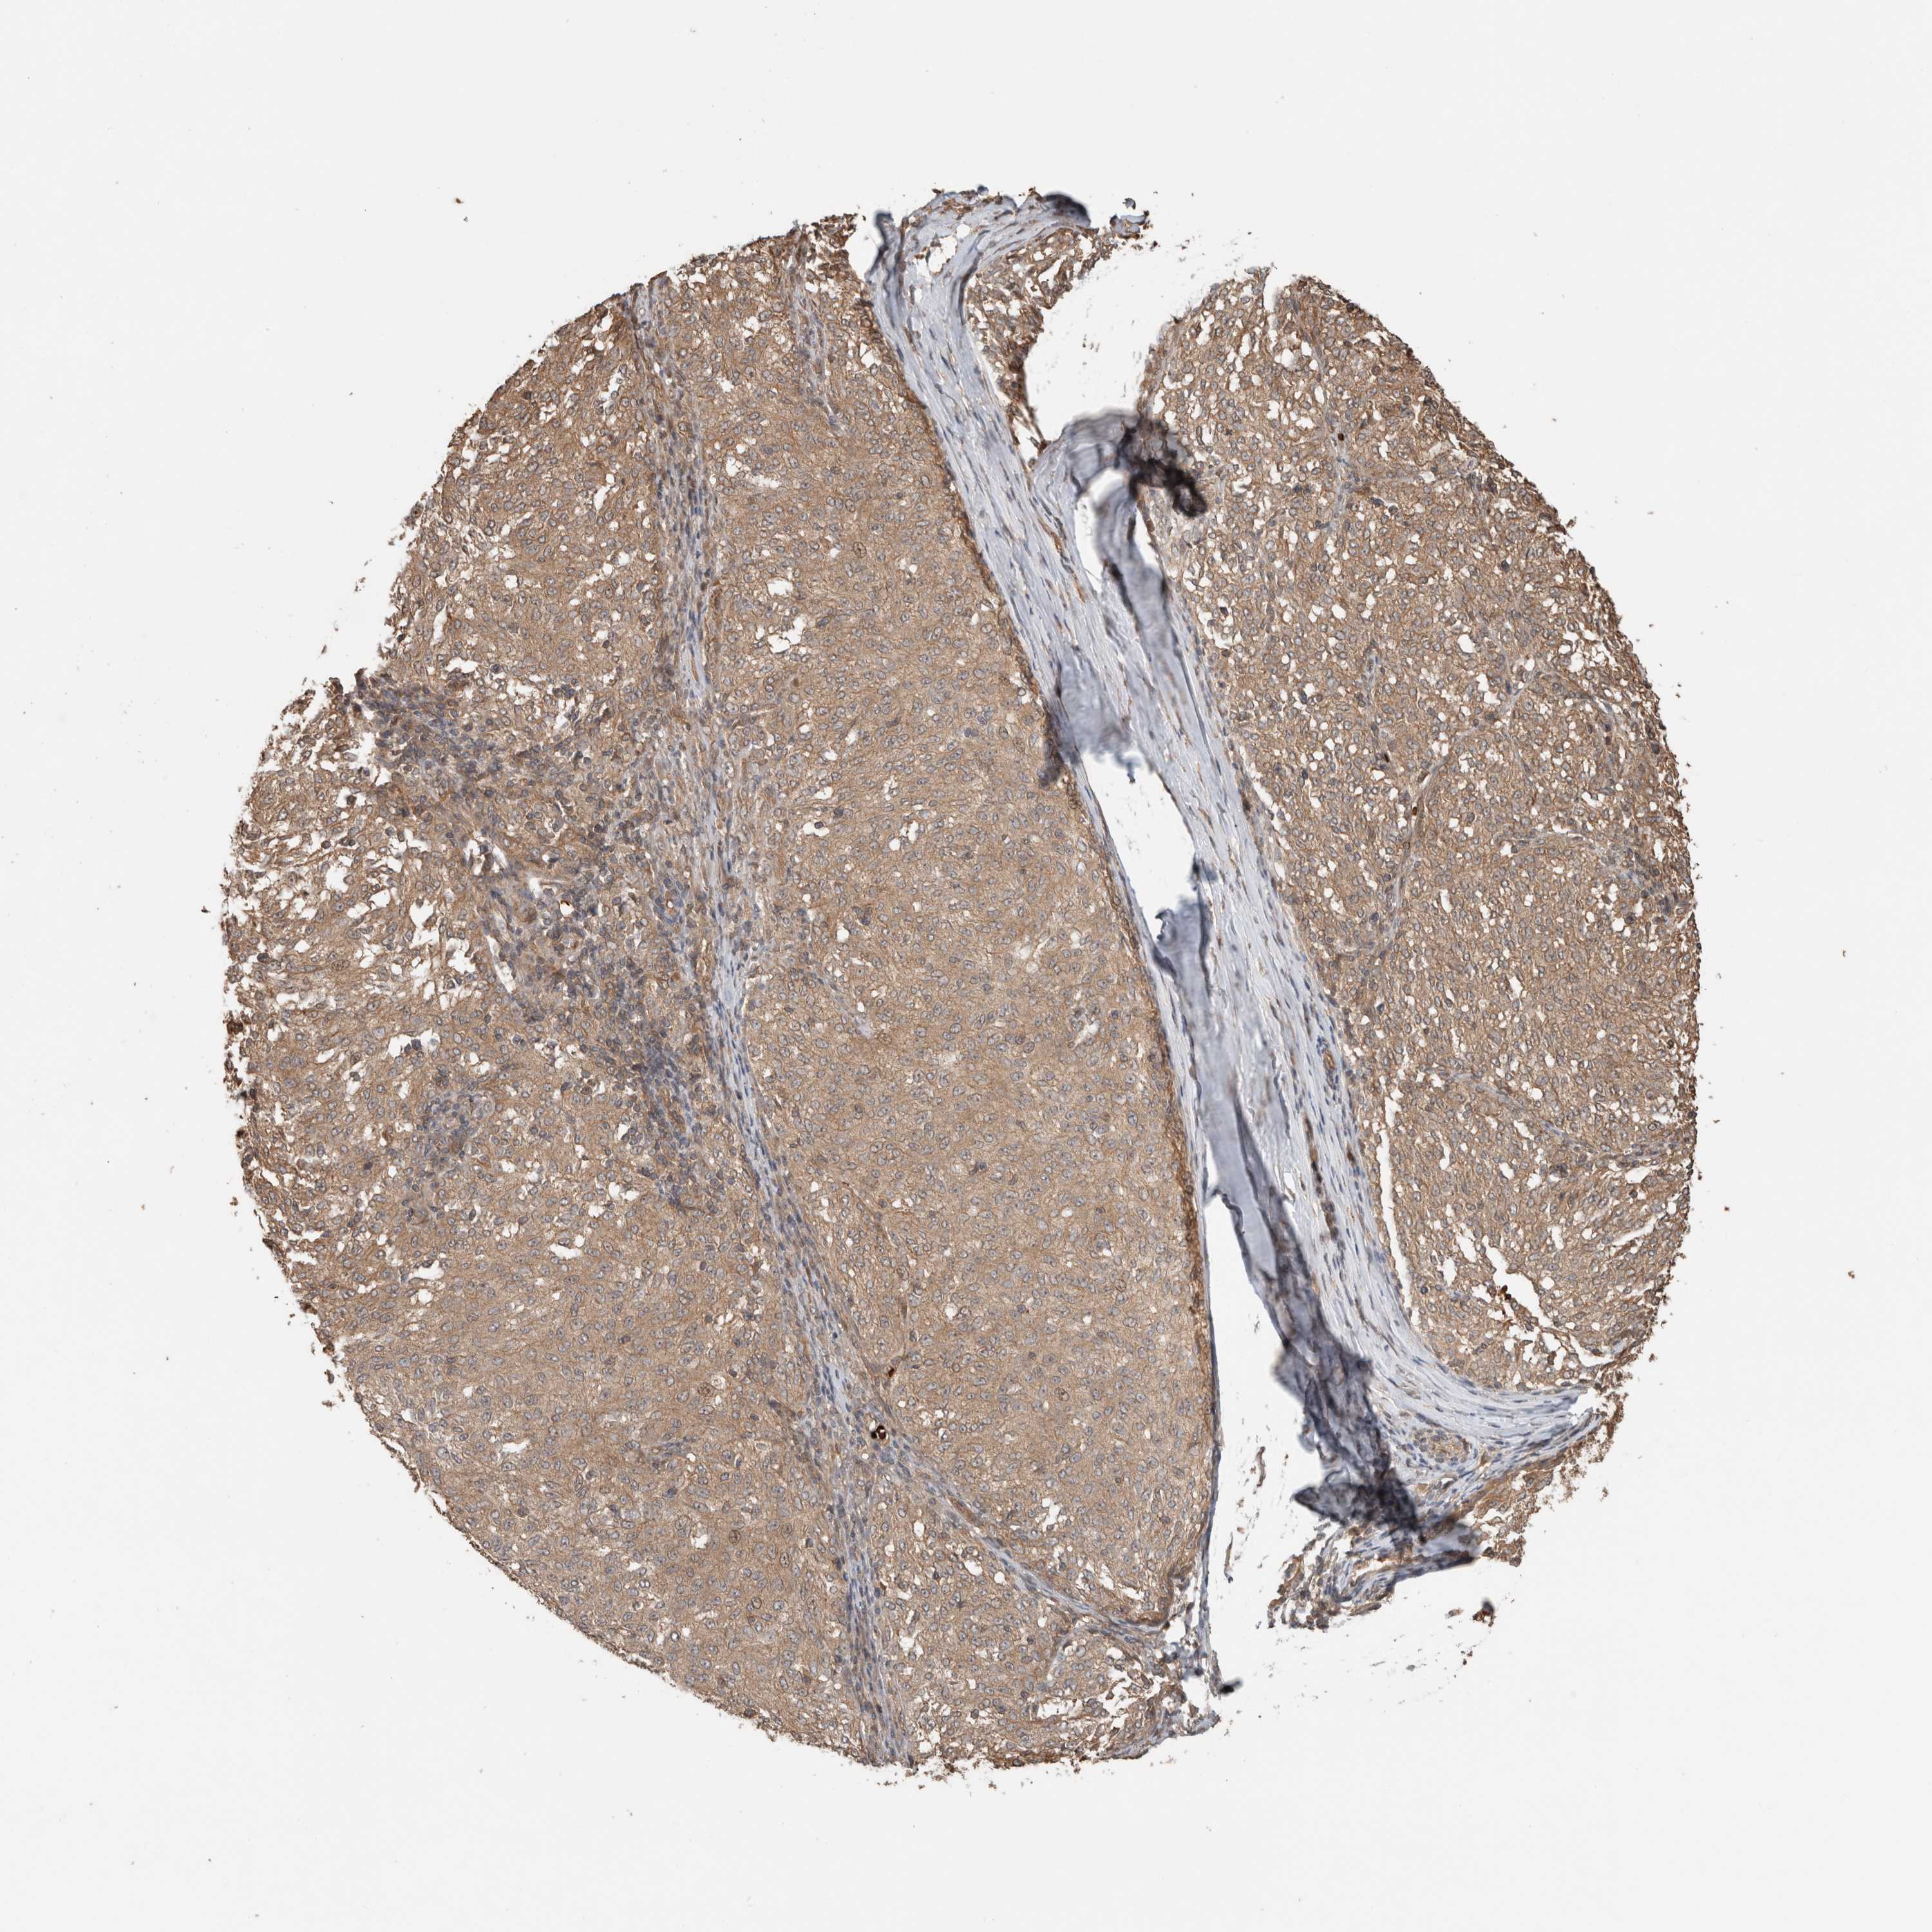

MELANOMA - Protein expressioni

A mouse-over function shows sample information and annotation data. Click on an image to view it in a full screen mode. Samples can be filtered based on level of antibody staining by selecting one or several of the following categories: high, medium, low and not detected. The assay and annotation is described here.

Note that samples used for immunohistochemistry by the Human Protein Atlas do not correspond to samples in the TCGA dataset.

Antibody stainingi

Antibody staining in the annotated cell types in the current human tissue is reported as not detected, low, medium, or high, based on conventional immunohistochemistry profiling in selected tissues. This score is based on the combination of the staining intensity and fraction of stained cells.

Each image is clickable and will lead to virtual microscopy that enables deeper exploration of all samples and also displays staining intensity scores, fraction scores and subcellular localization as well as patient and tissue information for each sample.

Antibody HPA024046

Antibody HPA024503

Antibody HPA024772

Staining

High

Medium

Low

Not detected

Intensity

Strong

Moderate

Weak

Negative

Quantity

>75%

75%-25%

<25%

None

Location

Nuclear

Cytoplasmic/membranous

Cytoplasmic/membranous,nuclear

Malignant melanoma, NOS

Malignant melanoma, Metastatic site